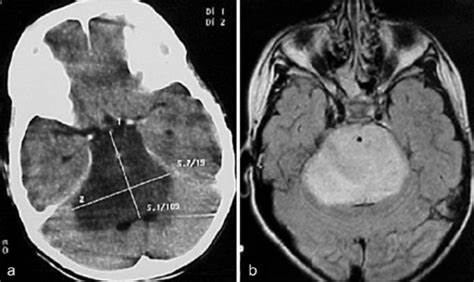

医生通过磁共振成像(MRI)检查诊断脑干胶质瘤。这些非侵入性测试使他们能够观察大脑内部是否存在肿瘤。他们也可以使用计算机断层扫描(CT),尽管这些测试通常不如核磁共振(mri)那么精确。